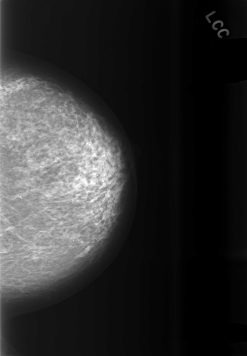

C_0474_1.LEFT_CC

LEFT_CC LINES 5696 PIXELS_PER_LINE 3944 BITS_PER_PIXEL 12 RESOLUTION 50 NON_OVERLAY